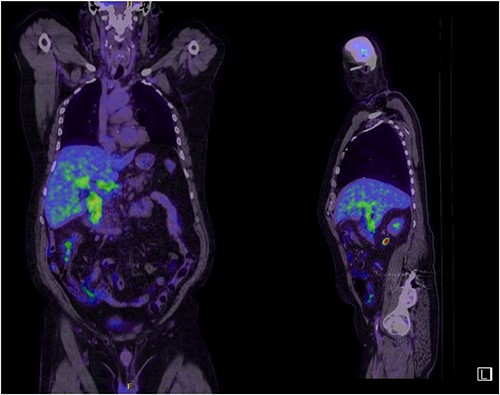

A man in his 70s presented to the emergency department with painless obstructive jaundice with dark urine and pale stools. The patient denied having any fever, nausea, vomiting, or weight loss. Liver function test progressively worsened during the admission peaking at a bilirubin of 287 umol/L (normal 2–20), alkaline phosphatase 694 U/L (normal 30–110), and alanine aminotransferase 160 U/L (normal < 40). Initial assessment on computed tomography and ultrasound raised concerns for primary pancreatic head neoplasm or cholangiocarcinoma (Fig. 1). He subsequently underwent magnetic resonance cholangiopancreatography (MRCP), which showed involvement of the entire common bile duct with no definite stricture or dilatation and no discrete pancreatic head mass (Fig. 2). Positron emission tomography showed abnormal uptake in the intrahepatic and extrahepatic bile ducts, focal uptake in the tail of the pancreas, and lymph nodes in the porta hepatis, retroperitoneum, and right iliac fossa (Fig. 3). Tumour markers revealed a carbohydrate antigen 19-9 (CA19-9) of 3286 kU/L (normal < 34).

Abnormal FDG uptake on PET scan extending from intrahepatic duct to distal common bile duct with uptake in the tail of pancreas.